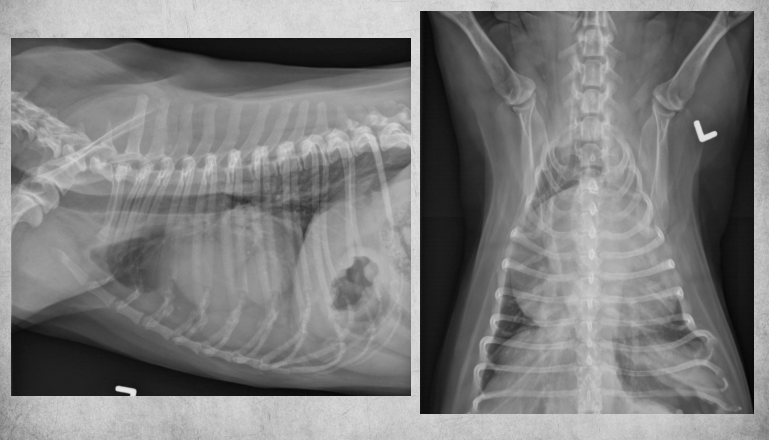

● 12 yo male castrated Shih-Tzu

● Geriatric check-up

● No clinical signs

congenital peritoneal-pericardial diaphragmatic hernia

these intestines are filled with gas due to

being empty

gastric axis also altered